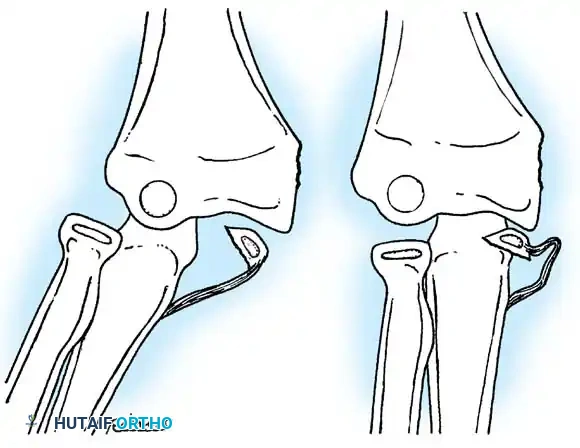

Fig. 33-39 A, Fracture occurring when elbow dislocation is reduced. B, Fractures occurring at time of elbow dislocation.

Fractures can present as angulated, translocated (shifted), or totally displaced. In the context of an elbow dislocation, the proximal fragment may become loose within the joint space or trapped, acting as a mechanical block to reduction.